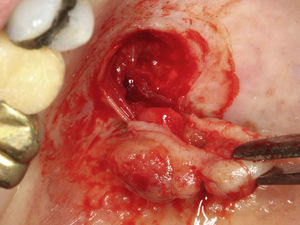

Casos clínicosCaso 1Paciente do sexo masculino, 68 anos de idade, leucoderma, procurou a Clínica de Estomatologia do Departamento de Odontologia da Pontifícia Universidade Católica de Minas Gerais (PUC Minas) queixando‐se de aumento de volume no palato, com tempo de evolução de 2 anos e discreta sintomatologia dolorosa. A anamnese não revelou alterações sistémicas. Ao exame clínico extraoral não foram observadas alterações. O exame clínico intraoral mostrou lesão nodular, pediculada, de consistência firme, localizada no palato duro do lado direito, entre os pré‐molares superiores e a rafe palatina, medindo aproximadamente 2cm na sua maior extensão. Foi realizada uma radiografia oclusal de maxila que não mostrou alterações ósseas. As hipóteses diagnósticas de neoplasia de glândula salivar e neoplasia mesenquimal benigna foram consideradas. Foi realizada biópsia incisional com diagnóstico anatomopatológico de adenoma pleomórfico. O tratamento proposto para a lesão foi a remoção cirúrgica conservadora. Paciente retornou após 4 semanas exibindo, ao exame intraoral, ulcerações na mucosa que recobria a lesão (fig. 1). Inicialmente, foi realizada anestesia local por meio da técnica supraperiosteal para bloqueio de ramos do nervo palatino maior, com cloridrato de lidocaína 2% e epinefrina 1:100.000 (ALPHACAINE 100®, DFL, Rio de Janeiro, Brasil). Em seguida, foi realizada incisão na base da lesão com bisturi lâmina 15 (Solidor, São Paulo, Brasil) e, após o descolamento do retalho mucoso palatino, a lesão foi exposta e removida (fig. 2). Foi realizada limpeza da ferida cirúrgica e sutura com fio seda Ethicon™ 4.0 (Johnson & Johnson, São Paulo, Brasil) (fig. 3). A lesão excisada (fig. 4) foi fixada em solução de formaldeído a 10% e enviada para exame anatomopatológico no Laboratório de Patologia Bucal da PUC Minas.

Paciente do sexo feminino, 31 anos de idade, leucoderma, foi encaminhada pelo cirurgião‐dentista à Clínica de Estomatologia do Departamento de Odontologia da PUC Minas para avaliação de lesão nodular no palato duro com diagnóstico histopatológico de adenoma pleomórfico, obtido por meio de biópsia incisional. Durante a anamnese, a paciente relatou a evolução da lesão há 4 anos com característica assintomática. Relatou estar no sexto mês de gestação e não apresentava outras alterações sistémicas. O exame extraoral mostrou ausência de alterações. Ao exame intraoral, observou‐se um aumento de volume bem delimitado no palato duro do lado direito, de consistência firme e coloração semelhante à da mucosa normal, medindo aproximadamente 2,5cm, exibindo pequena área de ulceração no local da realização da biópsia incisional (fig. 9). O exame radiográfico não mostrou alterações. O tratamento proposto foi a remoção cirúrgica conservadora e confecção de placa palatina em acrílico com grampos retentores para minimizar o desconforto pós‐operatório. Foi realizada anestesia local com lidocaína 2% e epinefrina 1:100.000 (ALPHACAINE 100®, DFL, Rio de Janeiro, Brasil), seguida de incisão semilunar com bisturi lâmina 15 (Solidor, São Paulo, Brasil) e rebatimento do retalho mucoso. Como a lesão se apresentava encapsulada, foi possível destacá‐la da mucosa suprajacente com facilidade (fig. 10). O retalho foi reposicionado por meio de pontos isolados (fig. 11) e a lesão (fig. 12) foi fixada em formaldeído a 10% para realização de exame anatomopatológico no Laboratório de Patologia Bucal da PUC Minas. Em seguida, foi colocada a placa de acrílico (fig. 13) para proteção da região operada e controlo da sintomatologia dolorosa.